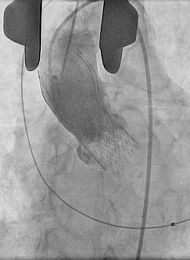

Medicos Argentinos realizan novedosa cirugía para reemplazar válvula cardíaca‏

Una paciente de 85 años se convirtió en la primera en el país en recibir una novedosa cirugía: un reemplazo de válvula aórtica a partir de la combinación de técnicas quirúrgicas y hemodinamia, empleando la arteria aorta...